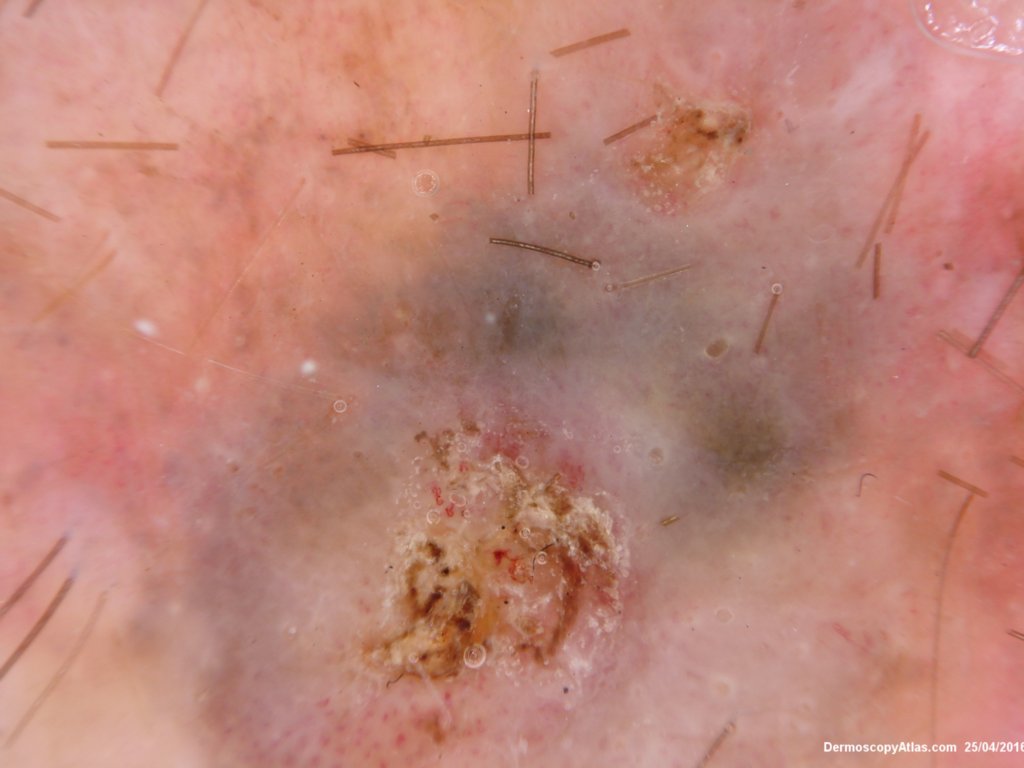

Site: Knee

Diagnosis: Melanoma invasive

Sex: M

Age: 57

Description: Lesion on the thigh

This 57 years old male presented with a lesion on his thigh that he said had only been present for 6 weeks. It looked and felt keratotic and had a bluish discolouration associated with it. It was thought to be an irritated Seborrhoeic keratosis perhaps with some bleeding into it to account for the blue colour.